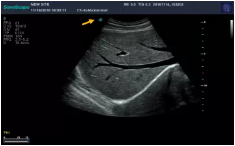

Mark點:每一把探頭都有一個mark點,是用于定位方向, mark點一側(cè)始終對應著圖像S點(圖像箭頭標識)一側(cè)。